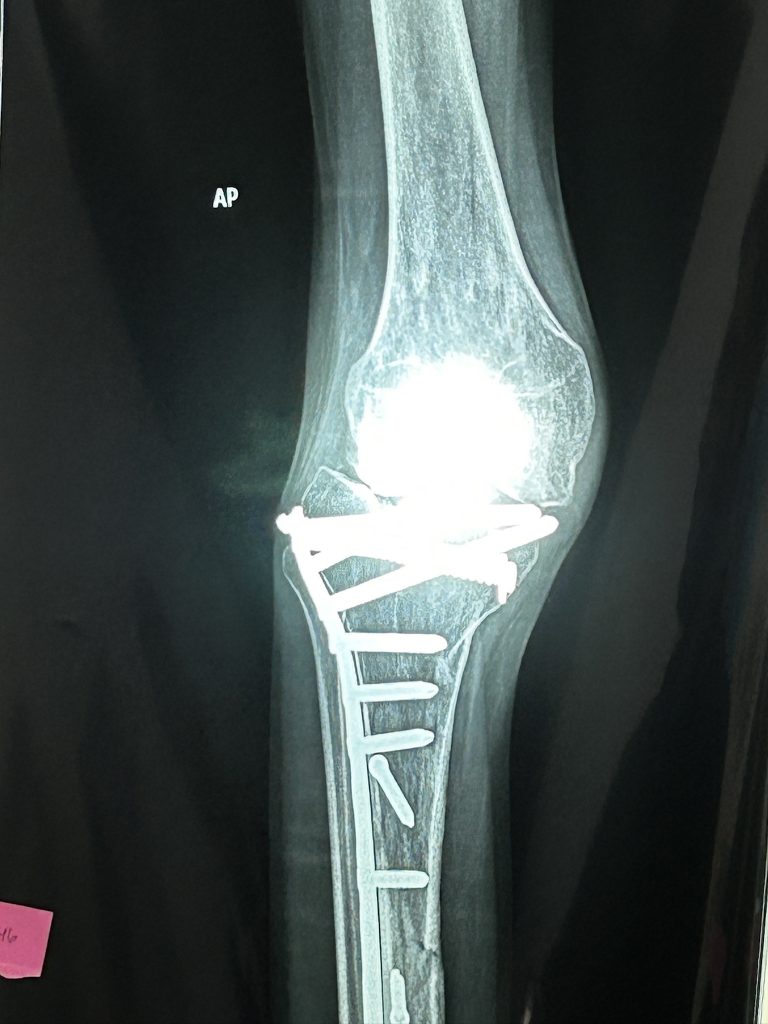

Fr. Chris Eggleton and I followed Dr. Jack Dawson and his Resident, Dr. Abdullah Ghali, as they evaluated the trauma patients. Most of them have old injuries from motor vehicle accidents, but a few have tumors. One young woman has a large cancerous tumor in her knee and will find out after biopsy whether there is any alternative besides amputation. Many of the problems from old accidents involve hardware inserted in initial surgeries that has either shifted or become infected. Most are seeking treatment because of pain and inability to walk properly. One young man had a leg injury from a gunshot wound after he and his father were targeted by a gang when they went to Guatemala City for work. His leg has healed perfectly even though the antibiotic nail in his femur was supposed to be temporary and usually needs to be removed. Since he’s fine, he won’t have to have another surgery after all.